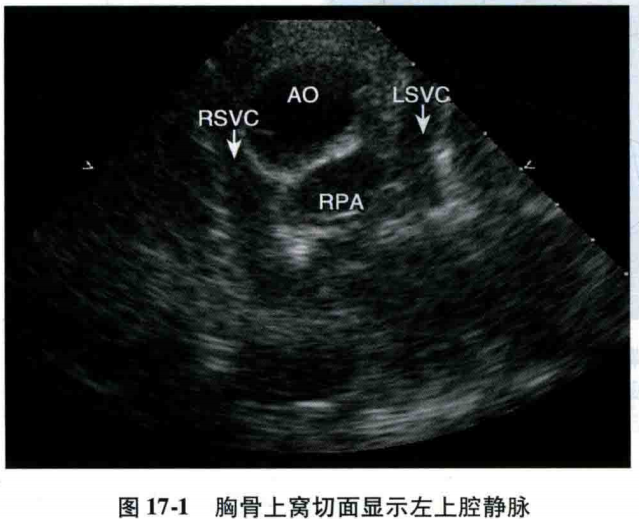

永存左上腔静脉图谱

永存左上腔静脉

永存左位上腔静脉

永存左上腔静脉示意图